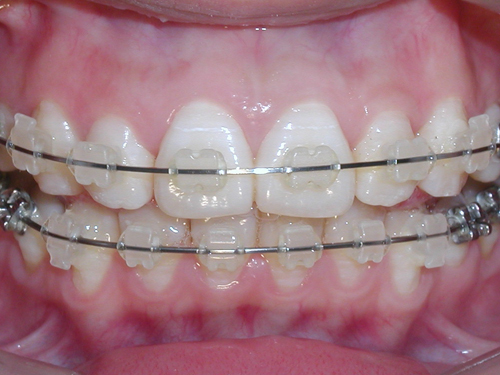

隐形陶瓷矫正

隐形陶瓷矫正

前牙开颌应该怎么办?在10岁前,通过破除不良习惯矫治器矫治,可带矫治器改正,开颌畸形有可能自行调正。在儿童时期,拾垫式活动矫治器和头帽颏兜垂直牵引,对矫治后牙牙槽过大者有效。固定矫治器如方丝弓、细丝弓矫治器,进行上下颌间垂直牵引,以升高前牙牙槽高度。有时也可压低后牙牙槽高度。年龄较大时,骨骼畸形明显的严重开颌,正畸和外科手术配合的方法能很好地治疗。